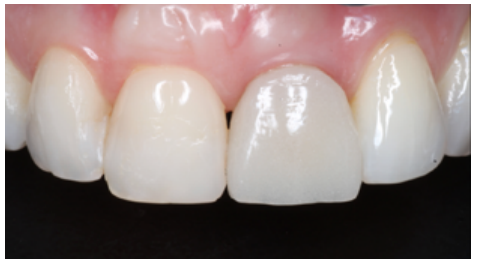

Clinical case: A 32-year-old female patient who attended for a possible root fracture of the upper left central incisor (ULCI), accompanied by a periodontal abscess at the bottom of the vestibule of the same tooth. A clinical and radiological examination established that the prognosis of the ULCI was unfavourable for conservative treatment. After evaluating the clinical features of the case, the treatment plan to extract the ULCI followed immediately by an osseointegrated implant (OII) and loading of a provisional prosthesis on the implant.

Conclusions: Rehabilitation on implants in situations of tooth loss in the aesthetic anterior sector, especially in young patients, requires a multidisciplinary treatment plan to extract the tooth and insert an OII in the correct 3-dimensional position. Various aspects need to be taken into account for this, particularly the residual remaining bone, the position of the gingival margin and preservation and conditioning of the peri-implant hard and soft tissues by means of grafts and proper handling of provisional prosthesis, until an ideal emergence profile and gingival contour is achieved before the final crown.

The benefits of immediate loading include a marked reduction in surgical interventions, less temporary dilation of the treatment and even better psychological and social wellbeing for the patient. In cases with a significant aesthetic requirement, immediate loading or provisionalisation, and post-extraction placement of the OII minimise alterations due to tooth loss and maintain the emergence profile, soft tissue contour and gingival papillae5-7.